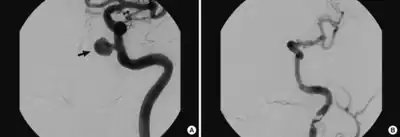

| Cerebral angiogram showing a transverse projection of the vertebrobasilar and posterior cerebral circulation. | |